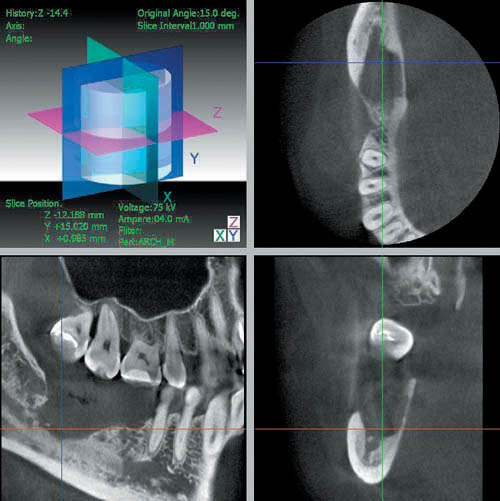

Стоматологический компьютерный томограф 3 DX Accuitomo/FPD дает высококачественное трехмерное цифровое изображение в трех плоскостях (горизонтальной, фронтальной и сагиттальной) с помощью ограниченного конического луча (в виде зоны объемом 6 см3), толщина среза может быть установлена от 0,125 до 2 мм.

Трехмерное изображение позволяет выполнять линейные и угловые измерения в трех плоскостях, определять денситометрическую плотность костных и мягкотканых структур, визуализировать нижнечелюстной канал, замыкательную кортикальную пластинку лунок зубов и дна верхнечелюстных пазух, височно-нижнечелюстные суставы, наружный слуховой проход, полость среднего уха и внутреннее ухо.

— расширяет возможности в диагностике височно-нижнечелюстных суставов, наружного слухового прохода, среднего и внутреннего уха (рис. 8).